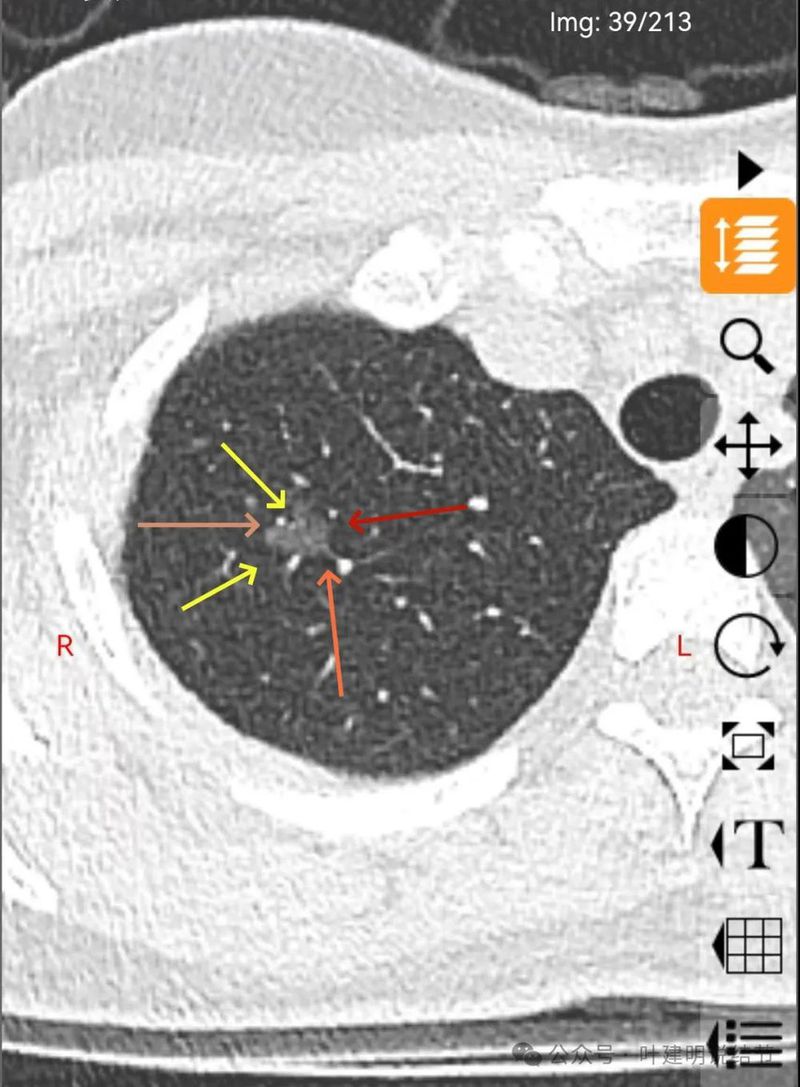

病灶密度稍不均,分叶明显,中间有扩张的细支气管,血管有贴边。整体轮廓与瘤肺边界清。

有实性成分出现。

混合密度,月牙铲征,轮廓清,血管多支进入,灶内实性成分明显,表面不平分叶,灶内细支气管扩张。